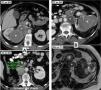

Se presenta como un tumor periférico circunscrito (pequeño y homogéneamente sólido o mayor quístico-hemorrágico) o como una lesión infiltrante e invasora de venas, con peor pronóstico.

Por su baja densidad vascular, el realce es menor que en otras neoplasias renales, lo que facilita su caracterización. En tomografía computarizada puede no realzar de manera concluyente, y entonces es indistinguible de un quiste hiperatenuante. La ecografía con contraste y la resonancia magnética son más sensibles para detectar vascularización. Son además característicos un patrón vascular específico, hipointensidad en T2, restricción de la difusión del agua y aumento de señal en fase opuesta.

It presents as a circumscribed peripheral tumor (small and homogeneously solid or larger and cystic/hemorrhagic) or as an infiltrating lesion that invades the veins, which has a worse prognosis.

Due to their low vascular density, papillary renal cell carcinomas enhance less than other renal tumors, and this facilitates their characterization. On computed tomography, they might not enhance conclusively, and in these cases they are impossible to distinguish from hyperattenuating cysts. Contrast-enhanced ultrasonography and magnetic resonance imaging are more sensitive for detecting vascularization. Other characteristics include a specific vascular pattern, hypointensity on T2-weighted images, restricted water diffusion, and increased signal intensity in opposed phase images.